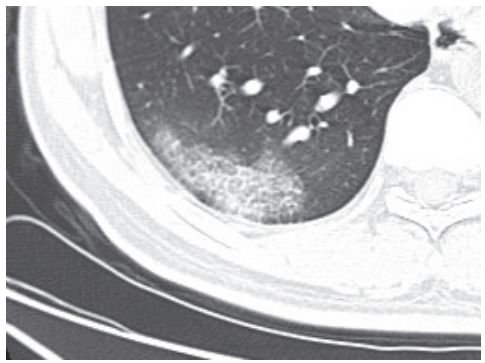

(六)吸入性肺炎

吸入性肺炎常见于慢性衰弱性疾病、咽和食管结构异常、全身麻醉等患者。吸入性肺炎可导致肺损伤或肺部炎症性疾病,如肺内节段性肺炎、支气管肺炎、肺脓肿和脓胸等。老年人存在隐性误吸。

影像学表现:无明显特异性特征,需结合病史与临床表现来做出诊断(图 3-20)。